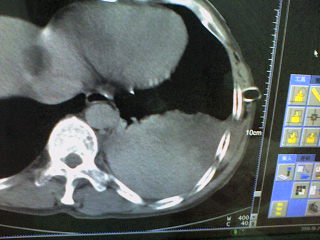

患者,男 51岁。突发性胸痛来诊。

起病急,症状重,应先除外心脏及大血管病变,左侧胸腔内可见囊实性病变,胸壁可见引流管影,建议提供完整的图像资料及相关的临床资料。

病变是胸腔内的。前部液体引出来的是血红色的液体。现在鉴别其后缘的高密度是什么?

这是一例胸膜外血肿形成的病例啊。。后面的高密度为凝血块。

手术证实的。